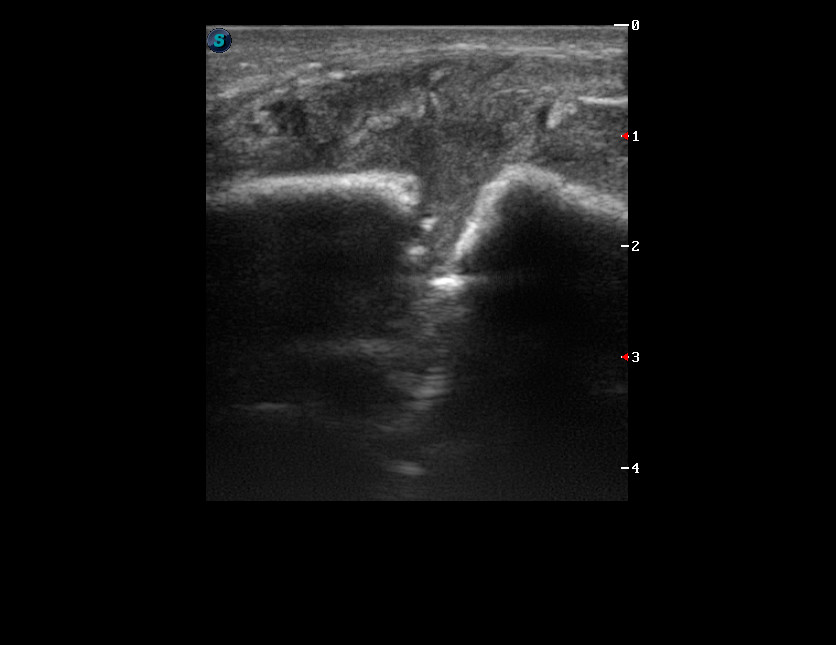

Перелом нижней челюсти

Молодой парень с припухлостью в области угла левой нижней челюсти.

Прислал ЛОР провести дифдиагноз между лимфаденитом и сиаладенитом.

--Травма была?

--ЫЫЫ. Месяц назад...